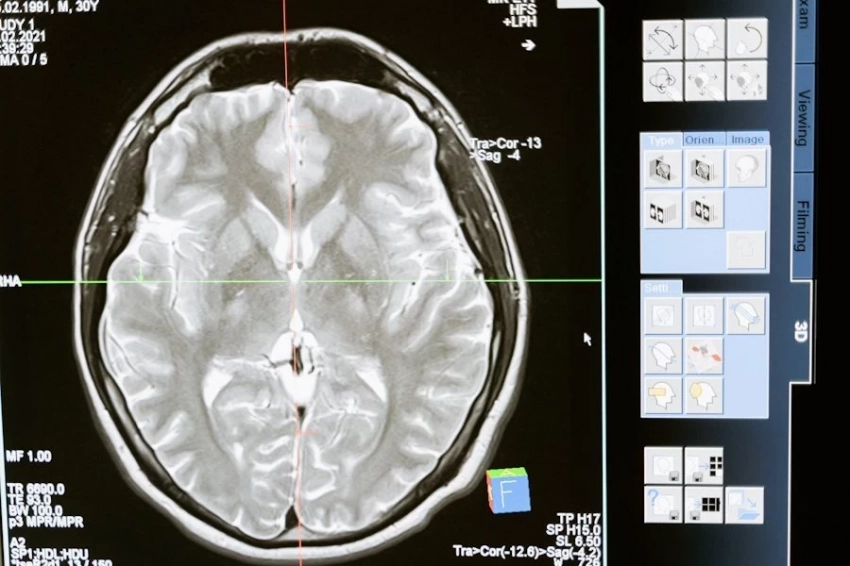

Фото из открытых источников Ученые Сеченовского университета приступили к разработке инновационных противоопухолевых препаратов, основанных на иммунных клетках самих пациентов. В рамках нового проекта специалисты планируют использовать Т-лимфоциты, которые уже самостоятельно модифицировались в организме и выбрали мишени для борьбы с опухолью. Как сообщили ТАСС в пресс-службе университета, исследование ведется совместно с Институтом персонализированной онкологии и Институтом регенеративной